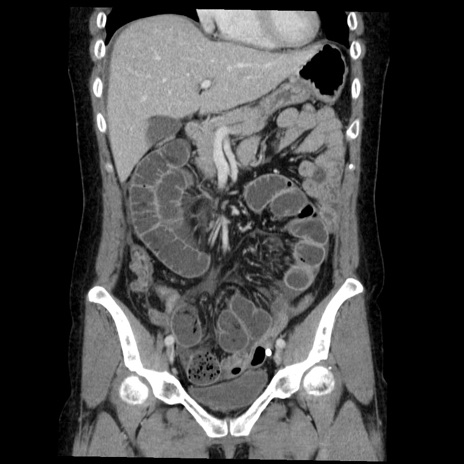

症例6(冠状断像)

【症例】50歳代女性

【主訴】下腹部痛

【現病歴】本日朝より下痢2回あり。 昼食を食べた後、嘔吐3回、下腹部痛認め、症状軽快せず、当院救急搬送。

最終食事:本日昼(生ものなし)。 昨日の夜、刺身を食ぺたとのこと。周囲に同様の症状の者なし。普段、排便は毎日あるとのこと。

【既往歴】卵巣癌術後(8年前に当院で卵巣摘出)

【身体所見】 意識清明、腹部:平坦、腸蠕動音→、やや硬、下腹部自発痛・圧痛あり、反跳痛あり、筋性防御なし。

【データ】WBC 16000、CRP 0.01